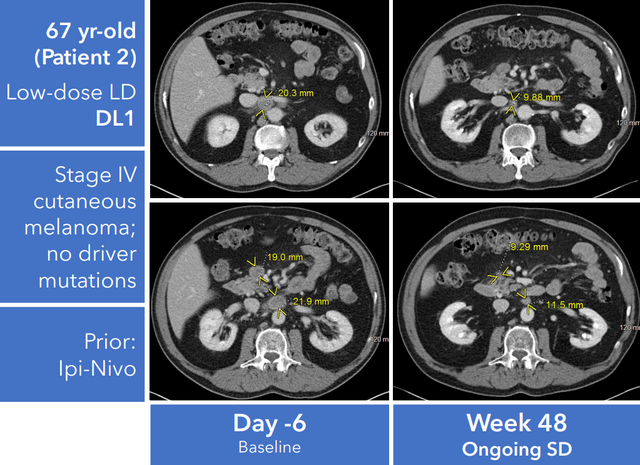

典型案例

一名67岁的晚期黑色素瘤患者,在接OBX-115治疗48天后,肿瘤显著缩小,实现病情稳定(SD)。